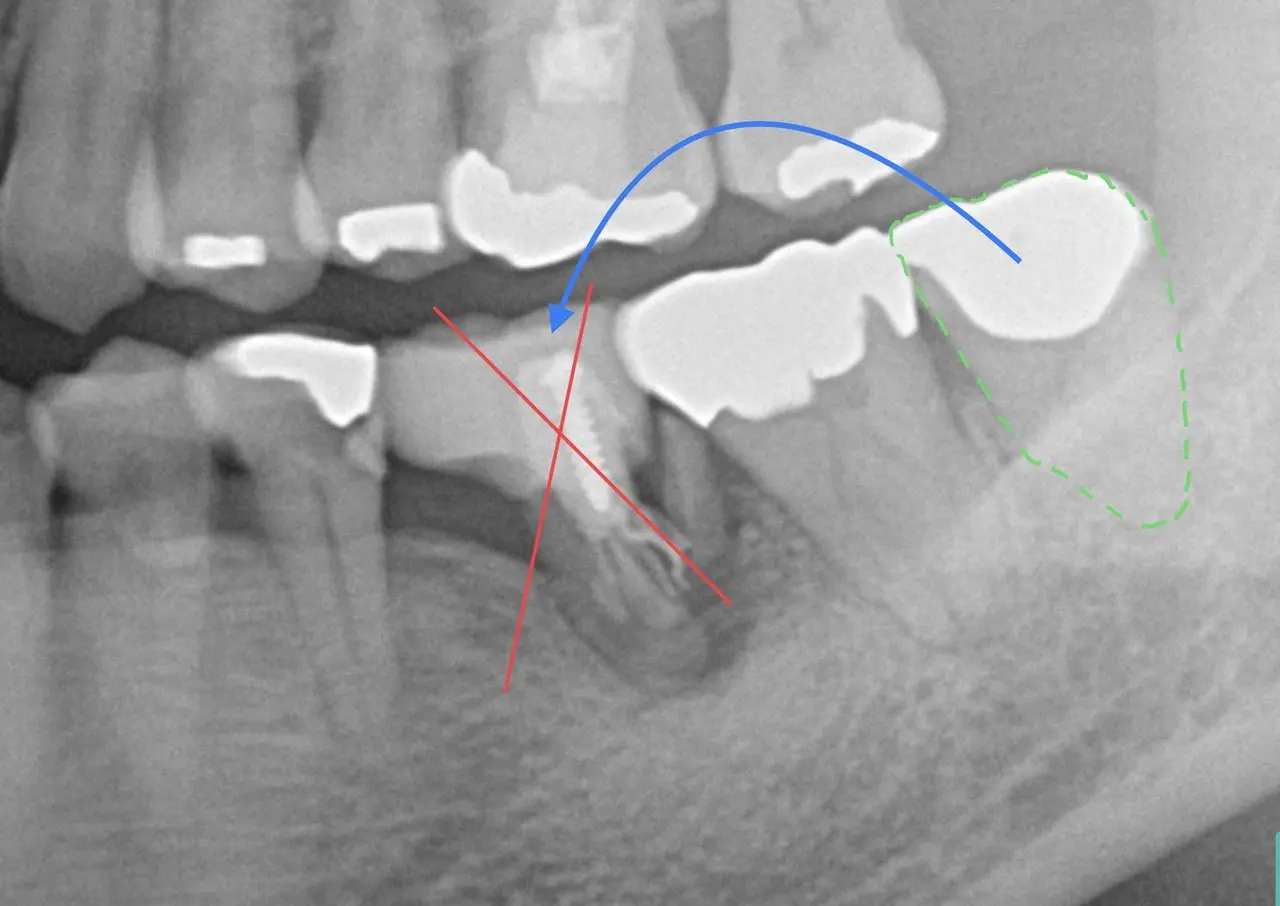

歯の移植

<歯の移植治療症例>

当院で行った歯の自家移植事例を紹介しています。